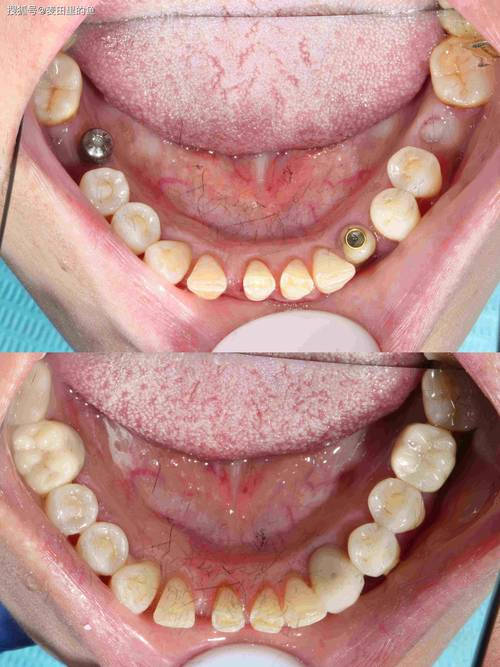

种植体(人工牙根)需要植入牙槽骨中,就像树木需要扎根在土壤里一样,牙槽骨的高度、宽度和密度直接决定了种植体能否稳固植入并长期承受咀嚼力。

- 种植体植入困难或失败: 没有足够的骨支撑,种植体可能无法获得初期稳定性,或者植入位置不佳,影响上部假牙的修复。

- 功能受限: 骨量严重不足时,即使勉强植入,也可能无法承受正常的咀嚼力,容易松动或折断。

现代口腔种植技术已经非常成熟,针对骨量不足有多种成熟的解决方案,核心思路就是增加骨量,也就是骨增量/骨增量手术,这就像在种植前先为种植体“搭积木”,创造一个稳固的基础。